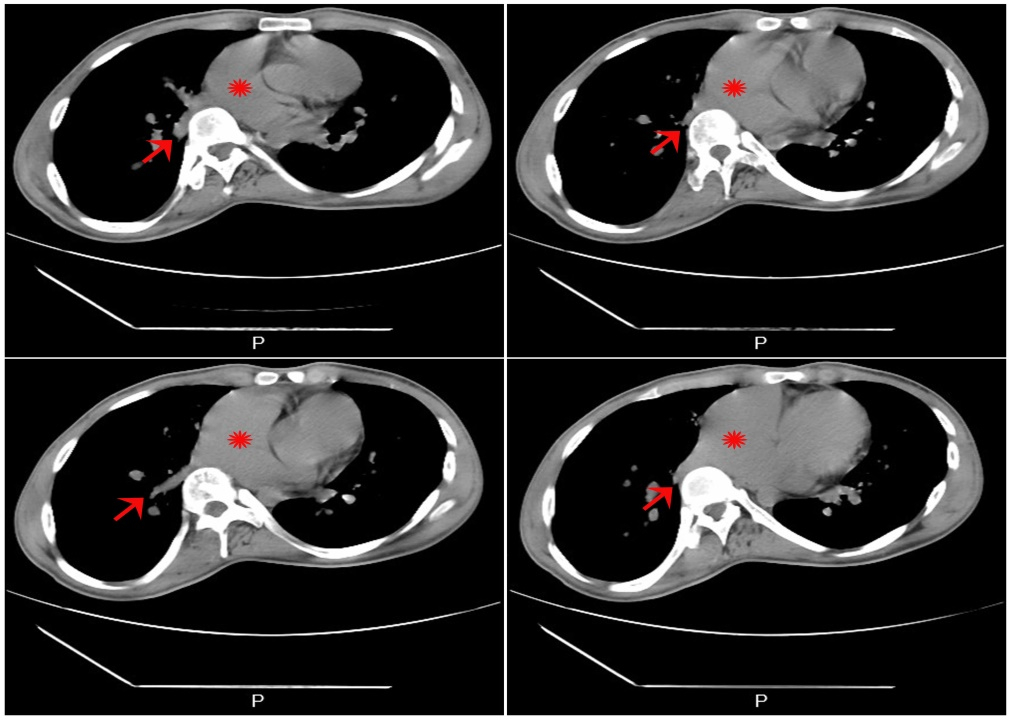

1 资料与方法患者,男性,21岁,于2022年5月18日收治本院,无明显不适主诉,15年前体检时发现ASD,长期门诊随访。患者近期门诊随访时外院心脏超声提示:房间隔缺损(继发孔型),右心增大,肺动脉增宽,轻度肺动脉高压(肺动脉平均压33 mmHg,1 mmHg=0.133 kPa),考虑患者房间隔缺损,存在手术指征,建议手术治疗,门诊以“房间隔缺损”收住入院。入院时查体:神志清楚,体温: 37.2℃,脉搏: 73次/min,血压: 109/66 mmHg,口唇无发绀,可见杵状指,颈静脉无怒张,双肺呼吸音清,未闻及明显干湿啰音,心律不齐,肺动脉瓣听诊区可闻及收缩期杂音,腹软,无压痛及反跳痛,肝脾肋下未及,双侧肾区无明显叩痛,脊柱侧弯,双下肢无水肿,神经系统检查阴性。血气分析氧分压:57 mmHg,血氧饱和度:88.7%,血、尿常规、生化、凝血项无殊。本院经胸心脏超声提示:先天性心脏病, 巨大房间隔缺损合并下腔静脉回流入左房(右向左分流),右心增大,轻度肺动脉高压,估测肺动脉收缩压(pulmonary artery systolic pressure,PASP)40 mmHg(图 1)。胸部高分辨CT平扫提示:心脏饱满,提示肺静脉异常引流,房间隔缺损可能,建议增强(图 2)。术前诊断:先天性心脏病:巨大房间隔缺损(下腔静脉侧及房顶部无房间隔残留组织),轻度肺动脉高压,完全性右束支传导阻滞,脊柱侧弯,胆囊内息肉。根据术前检查,决定进行心脏不停跳房缺修补术(人造补片)以及三尖瓣成形术。全麻后,沿胸骨正中切口开胸,切开右心房,术中所见:右心明显增大,房间隔缺损,下腔静脉无残端,大小约4.0 cm×5.0 cm,三尖瓣瓣环增大,约43 mm, 少量反流,未见肺静脉异位引流、室间隔缺损、动脉导管未闭、下腔静脉异位引流等心内其他畸形。手术体外循环下不停跳牛心包补片修补房缺,三尖瓣成形、置入28# SORIN成形环一枚(图 3)。术程顺利,术后即刻经食道超声未见房间隔明显残余分流,三尖瓣未见明显反流。心电图示窦性心律。术后给与头孢呋辛钠预防感染,护胃、化痰、利尿等对症支持治疗。术后经胸心脏超声提示:房间隔缺损修补术后,房水平未见残余分流,三尖瓣成形术后(图 4)。手术前后左心功能未见明显异常(表 1)。经1周治疗后,患者恢复良好,血气分析氧分压:141 mmHg,血氧饱和度:99.9%,予带药出院。

| CT示: 心脏饱满,提示肺静脉异常引流,房间隔缺损可能,建议增强。CT不同层面红色箭头:右下肺静脉;红色星号:心房 图 2 患者术前肺CT结果 |